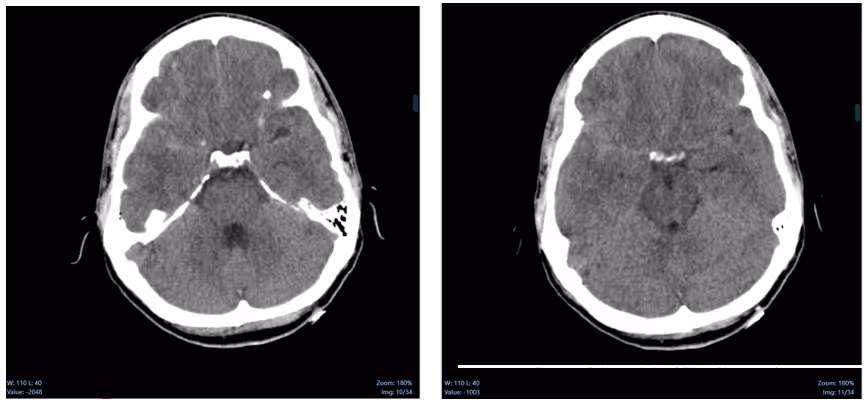

Ferrum Health partners with best-in-class AI providers offering solutions designed to reduce radiology workload and improve patient care.Avicenna Case Study: Intracranial HemorrhageAn intracranial hemorrhage was missed overnight.What if there was a tool that provided a second set of eyes?IntroductionIn the United States, intracranial hemorrhages occur in about 12-15 per 100,000 individuals, which results in approximately 7,000 surgical operations for hemorrhage evacuation. Timely and accurate diagnoses are necessary for the management of acute ICH patients. For example, prompt identification of ICH patients would facilitate immediate action, including control of blood pressure during the vulnerable first few hours of symptom onset or even surgical evacuation. In this context, reducing the risk of missing a finding is essential.Clinical CaseA 39-year-old man arrived at 3:00 AM with the Emergency Medical Services. The patient was found face down in the street with bleeding from the back of his head and ears. He presented with loss of consciousness and somnolence at his hospital arrival. An immediate NCCT of the head was ordered and obtained. The overnight report only noted a right posterior temporal occipital fracture.

At 7:00 AM the attending radiologist reviewed the case and also observed a subtle acute traumatic subarachnoid hemorrhage.If CINA-ICH was deployed at this hospital, in less than 1minute after the NCCT acquisition, a new DICOM series would have been added to the study with the suspected ICH identified by the software and the case would have been prioritized helping the fellow into his diagnosis.